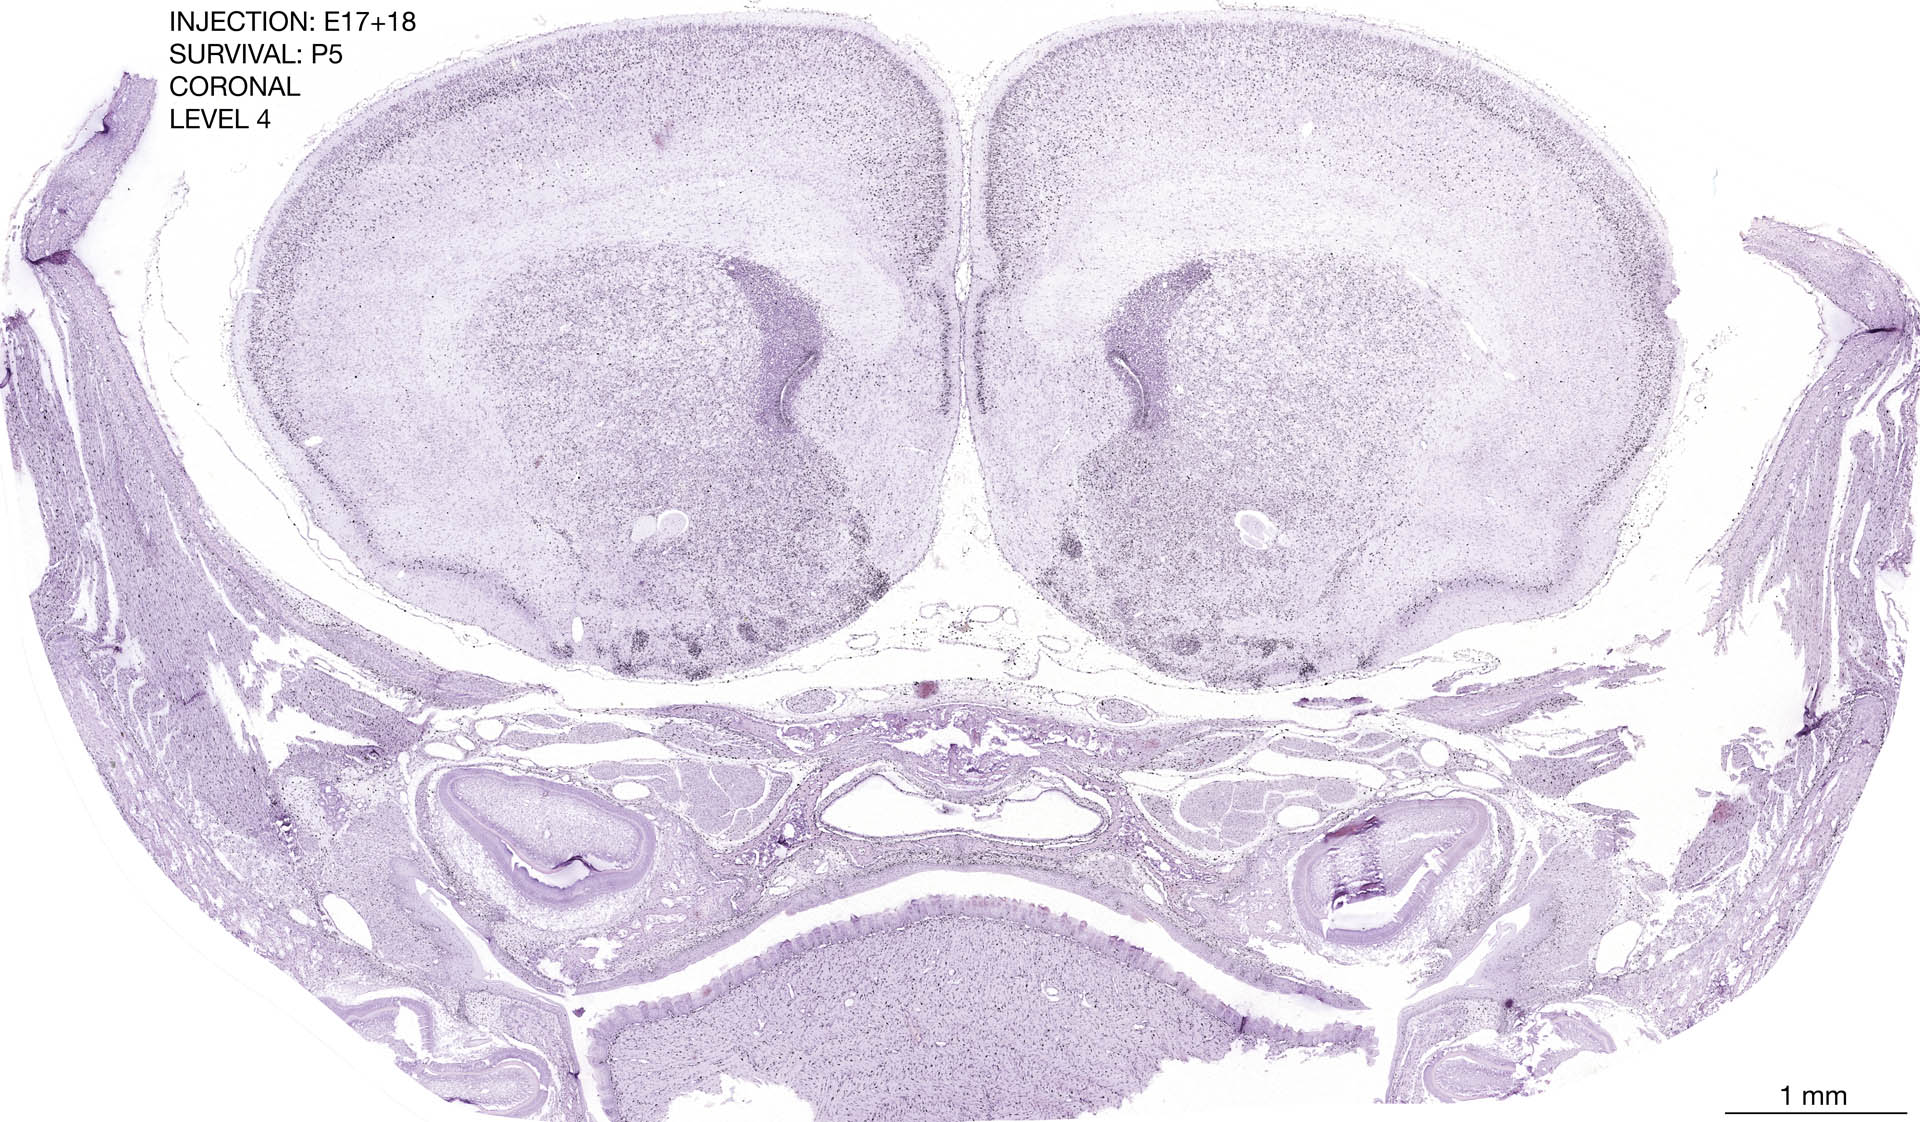

E17+18 P5 Survival The images below are from the brain of a rat that was exposed to tritiated thymidine on E17+18 and survived to P5. Download: Large | High Res Download: Large | High Res Download: Large | High Res Download: Large | High Res Download: Large | High Res Download: Large | High Res Download: Large | High Res Download: Large | High Res Download: Large | High Res Download: Large | High Res Download: Large | High Res Download: Large | High Res Download: Large | High Res Download: Large | High Res Download: Large | High Res Download: Large | High Res Download: Large | High Res Download: Large | High Res Download: Large | High Res Download: Large | High Res Download: Large | High Res Download: Large | High Res Download: Large | High Res Download: Large | High Res Download: Large | High Res Download: Large | High Res